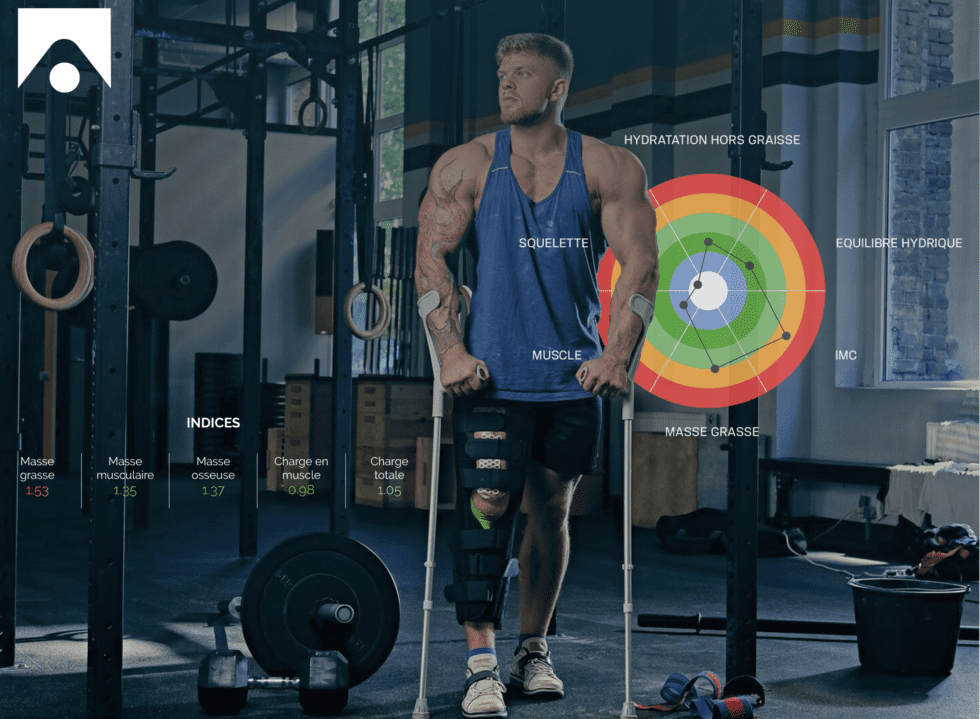

Bio-impédancemétrie et signes d’une activité physique excessive

Les adaptations physiologiques liées à l’entraînement nécessitent d’appliquer un stress physiologique d’une intensité suffisante pour provoquer une adaptation sans que celui ne soit trop intense pour l’organisme. Par conséquent, il est nécessaire de contrôler que la charge d’entraînement (intensité et volume) ne soit pas trop importante pour l’individu, ce qui favorise ainsi l’apparition d’une fatigue chronique et/ou de blessures.